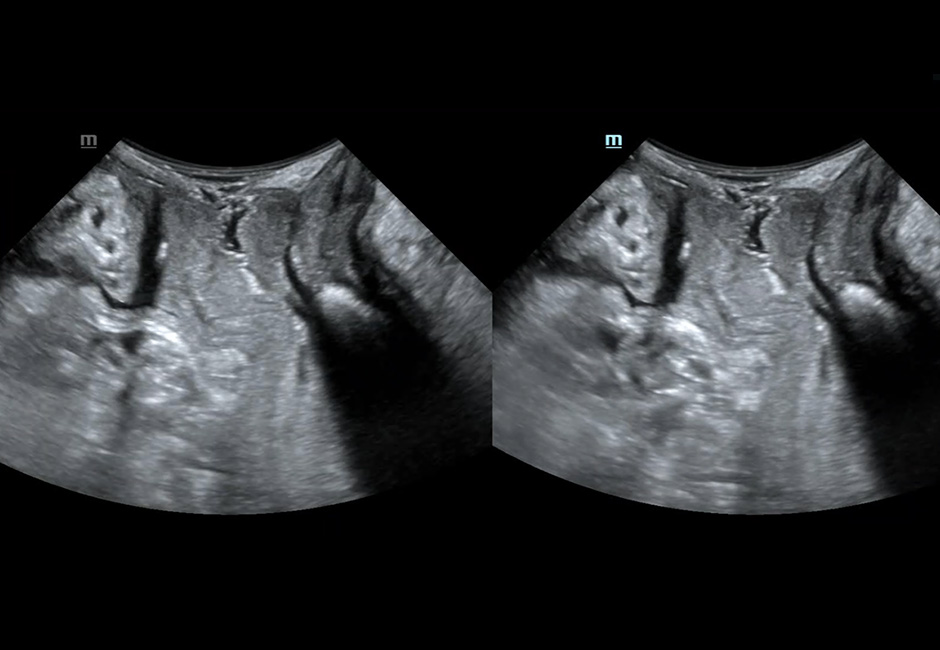

Midsagittal Plane From Rest to Maximal Valsalva

Render Mode Imaging of Levator Hiatus at Contraction